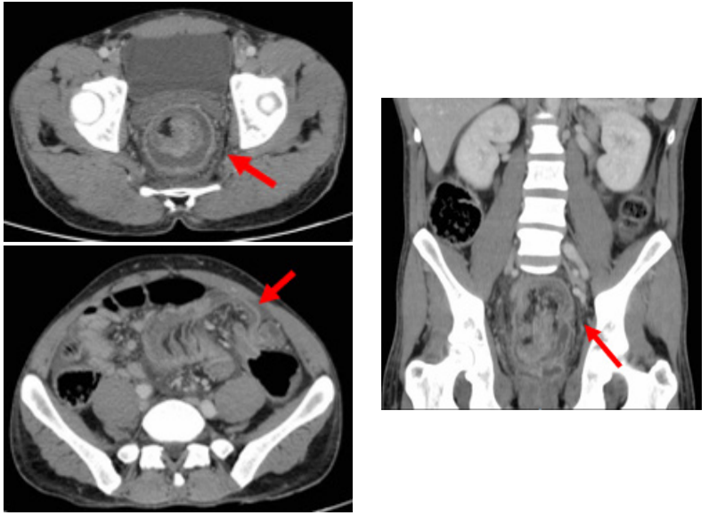

Varón de 39 años, natural de Marruecos, sin antecedentes de interés, que acude a urgencias por cuadro clínico de 15 días de dolor abdominal, asociado a vómitos intermitentes, deposiciones diarreicas y rectorragia, con empeoramiento progresivo hasta presentar obstrucción intestinal de 48 horas de evolución. La radiografía abdominal mostró dilatación marcada del colon (figura 1), que se corroboró con la TC abdominal (figura 2), donde además se visualizó una extensa invaginación a nivel del colon sigmoides, sin clara lesión subyacente, condicionando una oclusión mecánica con distensión retrógrada (ciego de 8 cm de diámetro con válvula competente). No se identificaron neumoperitoneo ni otros signos de perforación.

Figura 2. Tomografía computarizada abdominopélvica, con 2 secciones axiales y 1 sección coronal. La “imagen en diana” señalada por la flecha roja representa la invaginación colónica.